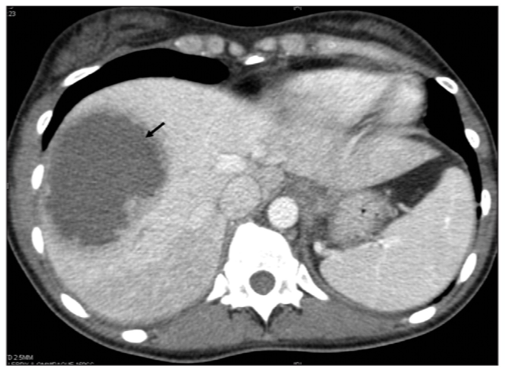

CT scan abdomen showing pyogenic abscess in the right lobe of the liver

2. imaging: chest x-ray will show elevation of diaphragm and basal lung lobe collapse. ultrasound and CT scan is used to define the abscess.